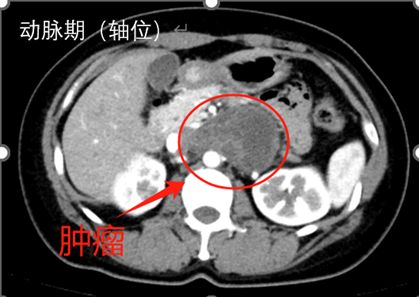

l CT:腹膜后偏左囊实性团块,边界清,增强实性部分不均匀轻中度强化,5.3*7.8*5.9cm,临近组织受推压。

7. 分离顺序:上极→内侧→下极→外侧→向中心。肿瘤上极见多支穿支血管进入肿瘤,其中包括一支粗大血管进入肾脏,复习术前影像,考虑可能为挤压变形的肾动脉,遂保留。

a) 术前细致的影像学评估,判断累及的器官及大血管走向,做到胸中有数。本例虽为神经鞘瘤,增强CT强化不明显 ,但较大肿瘤压迫导致回流不佳形成较多侧支循环,分离时应轻柔精细操作,及时电凝、夹闭或缝扎血管减少出血。肿瘤占位作用也导致正常血管移位(例如上极的肾动脉、肿瘤前上方的肠系膜上动脉),需严格保护。术前需反复阅片。